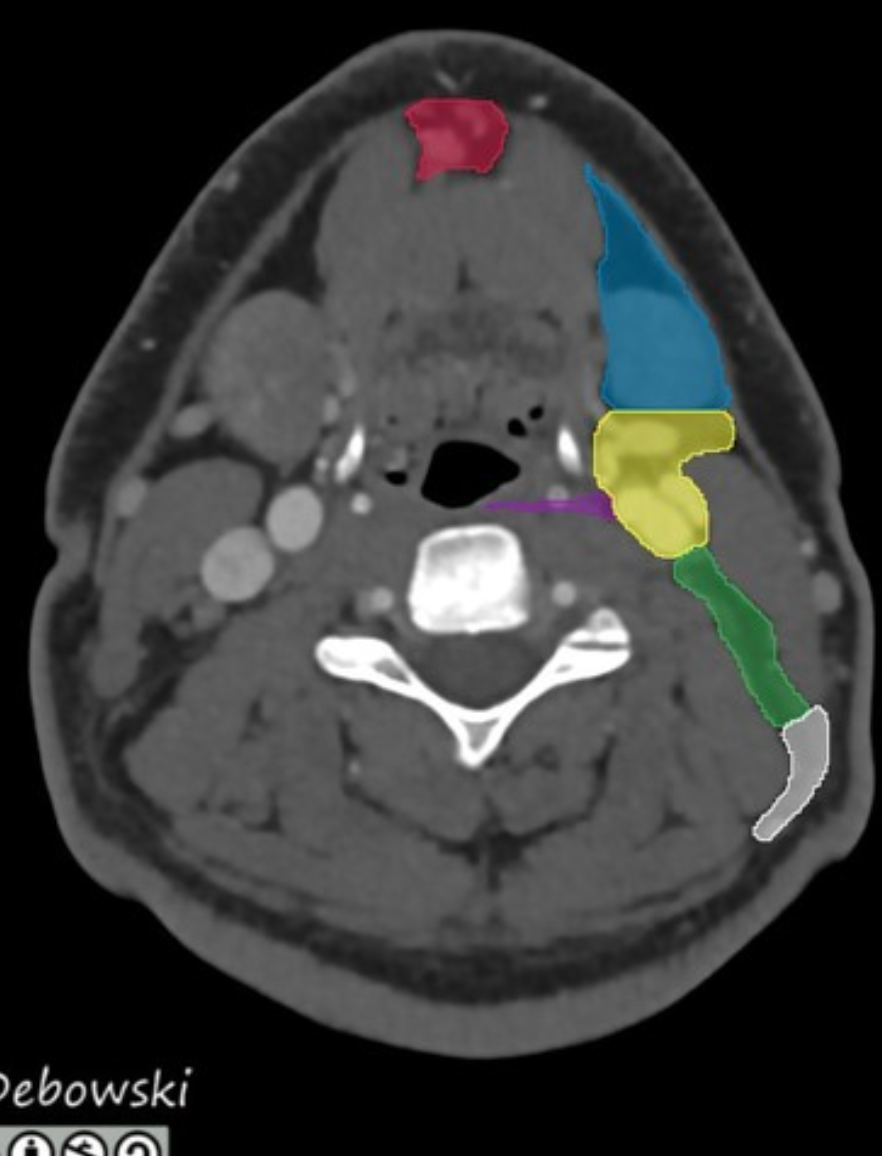

Level II: upper internal jugular (deep cervical) chain

superiorly: base of the skull at the jugular fossa

inferiorly: inferior border of the hyoid bone

anteriorly: posterior border of the submandibular gland

posterolaterally: posterior border of the sternocleidomastoid muscle

medially: medial border of the internal carotid artery

There are two sublevels:

level IIa: inseparable from or anterior to the posterior edge of the internal jugular vein; includes jugulodigastric nodal group

level IIb: posterior to and separable by a fat plane from the internal jugular vein